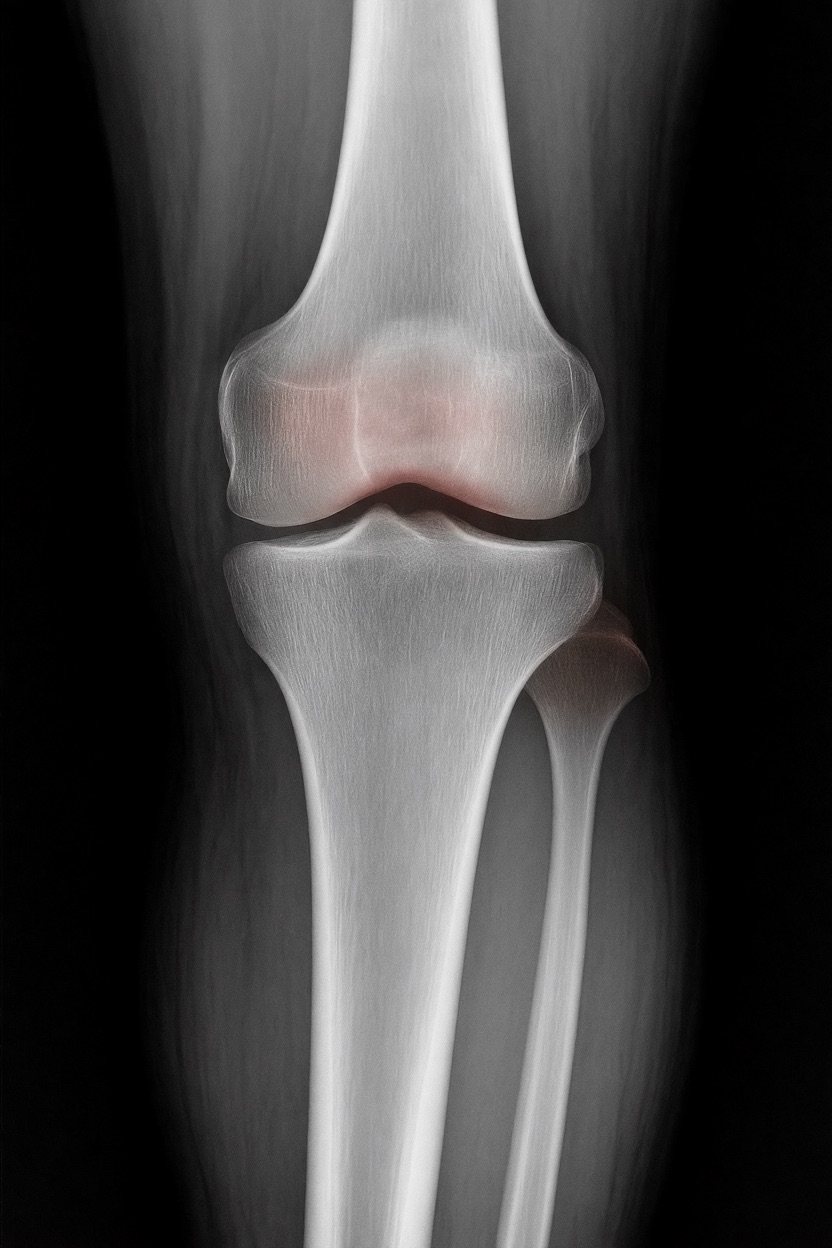

アートや写真の編集用に設計されたFlux Kontextのようなモデルを、医療画像、たとえば「単純な」骨折の赤色マーキングに使用できるか?

即答:面白い結果を出すが、過剰に反応し、医療ツールとしては信頼性に欠ける。これはアイデアを試すためのプロトタイプに過ぎない。

もちろん、このツールはオープンソースで、高速(1回の分析に25秒)、一般のデスクトップPCで動作するため、今後このコンセプトをさらに実験する価値はあると思います…今後の展開に注目です!

お楽しみください!